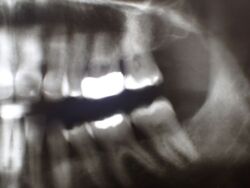

In diesem Zusammenhang wurde heute noch ein Übersichtsröntgenbild erstellt, dass einen ganz typischen, aber häufig nicht bekannten Befund mit sich bringt.

Obwohl die Patientin erkennbar eine gute Mundhygiene beteibt, zeigt sich im gesamten Oberkiefer und hier vor allem im Bereich der Backenzähne ein ausgeprägte und altersuntypisch weit voran geschrittener Knochenabbau.

Das Typische an diesen Zuständen besteht darin, dass der Knochen im Unterkiefer weitgehend normal erscheint, was bene gerade dafür spricht, dass es sich um kein mundhygienebedingtes Problem des Kieferknochenabbaus handelt.